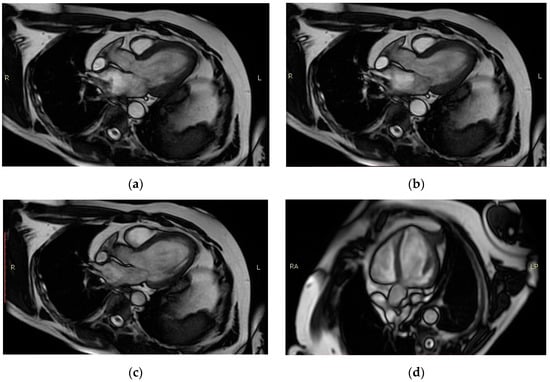

| Left Ventricle (LV) | Right Ventricle (RV) | ||

|---|---|---|---|

| LV ejection fraction | 30% | RV ejection fraction | 48% |

| Stroke volume | 48.2 mL | Stroke volume | 51.3 mL |

| End-diastolic (ED) volume | 160 mL | End-diastolic volume | 106 mL |

| End-systolic (ES) volume | 112 mL | End-systolic volume | 54.6 mL |

| Heart rate (HR) | 48 bpm | HR | 48 bpm |

| Mass ED | 83 g | Standard deviation HR | 1 bpm |

| Cardiac output | 2.3 L/min | ||

| Mass | 83 g | ||

| Mass ES | 88 g | ||

| End-diastolic epicardial volume | 239 mL | ||

| End-systolic epicardial volume | 196 mL | ||

| Standard deviation HR | 1 b pm | Flow Qp/Qs | 0.967 |

| Ant. sep. wall thickness | 0.9 cm | ||

| Inf. lat. wall thickness | 0.7 cm | ||

| End-diastolic dimension | 5.8 cm | ||

| End-systolic dimension | 4.8 cm | ||

| Fractional shortening | 16% |